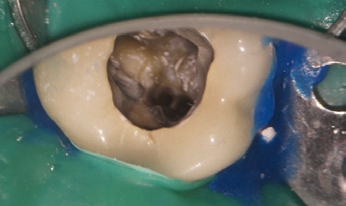

Eine 52-jährige Patientin wurde vom Hauszahnarzt mit der Bitte überwiesen, vor geplanter prothetischer Versorgung eine endodontische Revisionstherapie am Zahn 36 durchzuführen (Abb. 1). Der Zahn reagierte auf die Sensibilitätsprüfung mit CO2-Schnee negativ, auf Perkussion stark positiv. Die endodontische Diagnose lautete: Pulpastatus: pulpless and infected; periapikaler Status: symptomatic apical periodontitis.

Im Anschluss an die Aufklärung über die Behandlungsoptionen wünschte die Patientin die endodontische Revisionsbehandlung. Nach intraligamentärer Anästhesie und Applikation von Kofferdam wurde unter dem OP-Mikroskop (OMS2350, Zumax Medical, Jiangsu/China) die Zugangskavität mit dem Diamantinstrument 15802* und anschließend dem EndoGuard (H269QGK*) angelegt. Die Darstellung des Pulpenkammerbodens und der Kanalorificien mit dem alten Obturationsmaterial erfolgte mit extralangen Rosenbohrern EndoTracer* (Abb. 2). Bei der intrakanalären Diagnostik konnte zudem in der distalen Wurzel ein zweites, bei der Primärbehandlung nicht aufbereitetes Kanalsystem dargestellt werden. Im koronalen Drittel wurde das alte Füllmaterial mit dem Endo ReStart-Opener (RE10L15*) entfernt, im mittleren und apikalen Drittel mit der Endo ReStart- Feile (RE05L21*), beides jeweils bei 300 Upm und einem Drehmoment von 1,8 Ncm ohne Einsatz eines Lösungsmittels. Die restliche Entfernung und das Sondieren der Kanalsysteme wurde mit Handfeilen bis zur ISO-Größe 012 (17525*) vorgenommen. Die Länge der Kanalsysteme wurde durch Handfeilen mit dem EndoPilot mobil endometrisch bestimmt (EP0013*). Es erfolgten die maschinelle Etablierung eines Gleitpfades mit dem PathGlider (PG03L25*) und die Aufbereitung der Kanalsysteme unter kontinuierlicher Spülung mit 6 % NaOCl (CanalPro NaOCl, Coltène/ Whaledent, Langenau). Die durch apikales Messen bestimmte Größe der Kanalsysteme ergab in den mesialen Kanalsystemen eine notwendige Aufbereitung bis zur ISO-Größe 035 und in den distalen Kanalsystemen bis zur ISO-Größe 045. Mechanisch aufbereitet wurde mit den F360-Feilen (F04L25*) im EndoPilot mobil bei 1,8 Ncm und 350 Upm (Abb. 3).